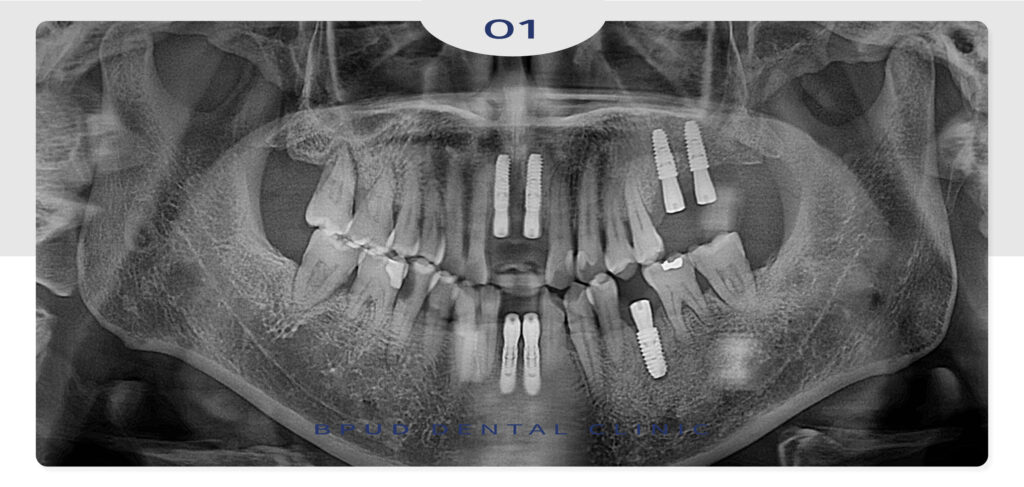

앞니 부위와 왼쪽 부위도 부족한 부분의

잇몸뼈 보충을 위해 상악동 거상술을 동반하여

임플란트 식립을 마쳤습니다.

상악동 거상술은 상악동의 바닥을 들어올려

그 공간에 뼈를 이식함으로써 잇몸뼈의 높이를

확보하는 수술을 말합니다.

앞니와 왼쪽의 치료를 마무리하시고는

오른쪽의 치료를 희망하셔서

부평임플란트를 진행하고 계신 상황입니다.